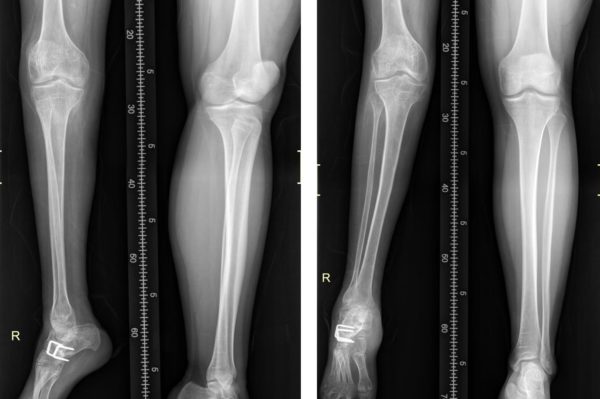

Опухоль на голени у Влада обнаружили еще в роддоме, в Иркутске. Первая операция была, когда Владику едва исполнилось 9 месяцев. А повторная понадобилась уже через месяц – опухоль выросла снова. Тогда же поставили диагноз – агрессивный фиброматоз. Фиброма – та самая доброкачественная опухоль, которая ничуть не лучше злокачественной. Во-первых, из-за крайне агрессивного характера: опухоль прорастает в кожу, органы, сосуды, нервы и кости очень быстро, при этом разрушая их. Во-вторых, удалить опухоль полностью практически невозможно – нет единого очага, а опухолевых узлов очень много.

В Москве диагноз подтвердили, но все же взялись лечить и лечили до 8 лет. Пробовали все: химиотерапию, лучевую терапию. Опухоль увеличилась до 20 см, разрослась до бедра, собираясь двигаться дальше, вверх по телу. Нога Влада постоянно была согнута в колене под прямым углом из-за давления опухоли, а после лучевой терапии с гипертермией (нагревом участка с опухолью свыше 39,5°С) правая нога вовсе перестала расти. В общем, лечение не помогло.

После Германии снова начались проблемы – сказались последствия той высокодозной лучевой терапии. Влад рос, а нога нет. Сначала она стала короче левой на пару сантиметров, потом на 7, сегодня – на 8. Владу нужна еще одна операция, и снова наисложнейшая, в России ее не делают. Прооперировать Влада могут в израильской клинике «Ассута». Операция будет вестись одновременно на трех участках ноги: Владу просверлят коленную чашечку, вставят в нее специальный гвоздь, который делается на заказ, и введут гвоздь в бедро.

В бедре сделают искусственный перелом, рассекут кость и вставят магниты. Так, по миллиметру в день, кость будет наращиваться, и нога вытягиваться. Одновременно выпрямят колено и вставят в него титановую пластину. А в стопе проведут ахиллопластику, вживив в нее мышцу из бедра – сегодня Влад почти не чувствует пальцев правой ноги. Еще полгода восстановительный период, а потом… потом наконец Влад встанет на ноги и сделает первый шаг. Впервые за 18 лет.